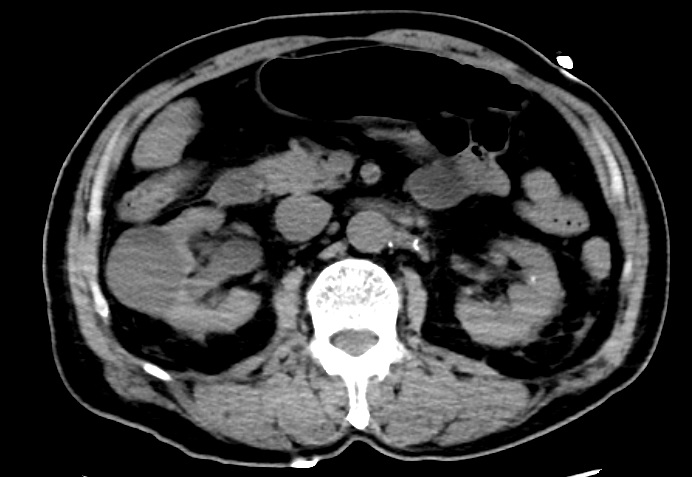

在有效的处理下,患者生命体征迅速稳定,行CT检查显示双肾周感染。